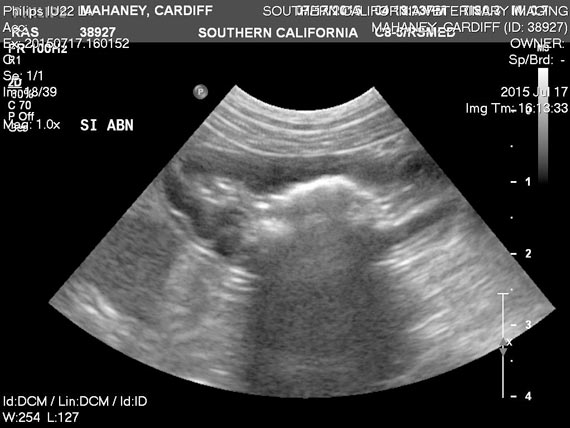

Is It Cancer Never Assume from www.veterinarypracticenews.com Diarrhoea (n = 13) was most common. If the tumor is large enough to cause a blockage, your dog becomes severely constipated. All dogs had clinical signs attributable to gi disease; Suspicious lumps or bumps we hear a lot about women giving themselves regular breast exams and checks, but you never really hear about checking your pet. Here are some of the signs of cancer in a dog or cat: Dogs suffering from gastrointestinal cancer might experience vomiting, diarrhea, appetite loss and weight loss. Ultrasonographic abnormalities were present in 8 of 13 dogs with abnormal wall layering (n = 7) and hyperechoic mucosal striations (n = 7) representing the most common findings. Bone cancer is also accompanied by a lot of swelling.

This is usually a severe lameness, where the dog cries in distress if you try to touch the sore place. Diarrhoea (n = 13) was most common. Red flag signs include severe lameness, swelling and character change. If the tumor is large enough to cause a blockage, your dog becomes severely constipated. Ultrasonographic abnormalities were present in 8 of 13 dogs with abnormal wall layering (n = 7) and hyperechoic mucosal striations (n = 7) representing the most common findings. Bone cancer is also accompanied by a lot of swelling. Small amounts of blood might appear in the vomit. Unsurprisingly, lameness is one of the main symptoms of bone cancer in dogs. Dogs suffering from gastrointestinal cancer might experience vomiting, diarrhea, appetite loss and weight loss. Suspicious lumps or bumps we hear a lot about women giving themselves regular breast exams and checks, but you never really hear about checking your pet. All dogs had clinical signs attributable to gi disease; In total, 14 dogs received some form of treatment. Here are some of the signs of cancer in a dog or cat:

Top 10 Warning Signs Of Cancer In Pets Hudson Veterinary Hospital from www.hudsonvet.com Bone cancer is also accompanied by a lot of swelling. Blood in the feces, or tarry, dark stools, could indicate the tumor is bleeding. In total, 14 dogs received some form of treatment. This is usually a severe lameness, where the dog cries in distress if you try to touch the sore place. Ultrasonographic abnormalities were present in 8 of 13 dogs with abnormal wall layering (n = 7) and hyperechoic mucosal striations (n = 7) representing the most common findings. Unsurprisingly, lameness is one of the main symptoms of bone cancer in dogs. Red flag signs include severe lameness, swelling and character change. Here are some of the signs of cancer in a dog or cat:

Bone cancer is also accompanied by a lot of swelling. Ultrasonographic abnormalities were present in 8 of 13 dogs with abnormal wall layering (n = 7) and hyperechoic mucosal striations (n = 7) representing the most common findings. Blood in the feces, or tarry, dark stools, could indicate the tumor is bleeding. Red flag signs include severe lameness, swelling and character change. Here are some of the signs of cancer in a dog or cat: In total, 14 dogs received some form of treatment. Small amounts of blood might appear in the vomit. Suspicious lumps or bumps we hear a lot about women giving themselves regular breast exams and checks, but you never really hear about checking your pet. Unsurprisingly, lameness is one of the main symptoms of bone cancer in dogs. This is usually a severe lameness, where the dog cries in distress if you try to touch the sore place. If the tumor is large enough to cause a blockage, your dog becomes severely constipated. Dogs suffering from gastrointestinal cancer might experience vomiting, diarrhea, appetite loss and weight loss. All dogs had clinical signs attributable to gi disease;

Unsurprisingly, lameness is one of the main symptoms of bone cancer in dogs. In total, 14 dogs received some form of treatment. Dogs suffering from gastrointestinal cancer might experience vomiting, diarrhea, appetite loss and weight loss. Small amounts of blood might appear in the vomit. Here are some of the signs of cancer in a dog or cat: All dogs had clinical signs attributable to gi disease; This is usually a severe lameness, where the dog cries in distress if you try to touch the sore place. If the tumor is large enough to cause a blockage, your dog becomes severely constipated. Suspicious lumps or bumps we hear a lot about women giving themselves regular breast exams and checks, but you never really hear about checking your pet. Blood in the feces, or tarry, dark stools, could indicate the tumor is bleeding. Diarrhoea (n = 13) was most common. Red flag signs include severe lameness, swelling and character change. Ultrasonographic abnormalities were present in 8 of 13 dogs with abnormal wall layering (n = 7) and hyperechoic mucosal striations (n = 7) representing the most common findings.